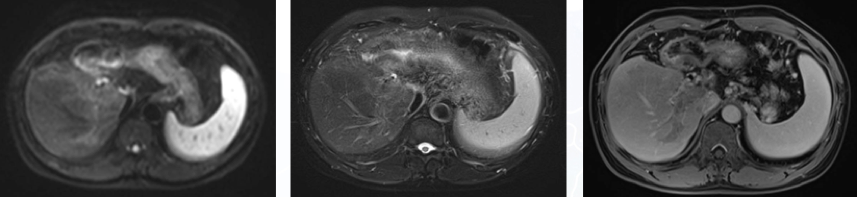

2021年1日13日我院复查MR,与2020年4月22日片比较:肝癌术后改变,残肝实质于增强扫描动脉期多发异常强化影,建议密切观察;增强后门静脉主干及其所见分支、所见肝静脉多发瘤栓形成,腹膜后多发淋巴结增大(图3)。

图3.2021年1月13日复查MR